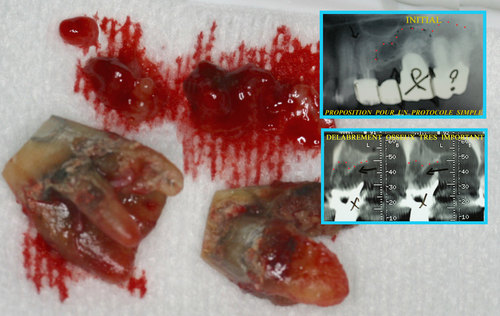

Les infections des dents provoquent des lésions osseuses avec disparition du volume osseux au fur et à mesure que l’infection se propage dans l’os des maxillaires. (fig. 29)

Fig. 29

Les infections dentaires provoquent des pertes osseuses importantes

Cela interdit souvent le port d’une prothèse correcte ou la mise en place d’implants en remplacement des dents absentes.

Un rayonnement laser pénétrant utilisé sous eau oxygénée à 10 volumes permet de décontaminer tout l’os du maxillaire après l’extraction des dents (fig. 30)

Fig. 30

Décontamination du maxillaire après extractions